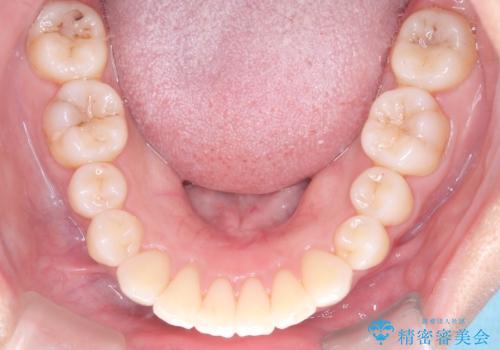

非抜歯で整える前歯の矯正

- 患者様は、前歯の重なり(叢生)が気になるとのことでご来院されました。診断の結果、奥歯を後方に移動することで前歯にスペースを確保し、非抜歯で歯列を整える方針としました。治療には審美性の高いホワイトワイヤーを使用し、奥歯の遠心移動にはリンガルアーチを装着しました。治療期間は約2年を予定し、月に一度の調整を通じて歯の動きを細かく管理しました。

非抜歯矯正は、歯を抜かずに自然な歯列を作るため、歯列全体のバランスを考慮する必要があります。本症例では、リンガルアーチによる奥歯の遠心移動を用いましたが、初期段階で軽い違和感を覚える方もいらっしゃいます。そのため、装置装着後のケアや食生活について詳しく説明を行い、患者様にも協力いただきました。また、審美ワイヤーを使用することで、日常生活での見た目のストレスを軽減し、治療を快適に進めることができました。